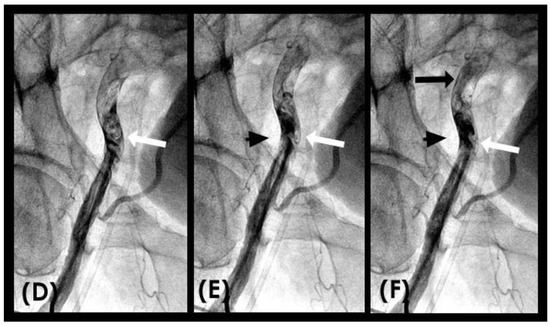

In the right coronary artery (RCA), with the novel angiographic technique, during diastole, the antegrade flow was clearly illustrated (Figure 9A–D). The leading edge of the flow was sharp, suggestive of laminar flow (Figure 9C). The speed in diastole was fast, as the blood could traverse from the end of the proximal segment to halfway through the mid-segment in just 0.067 s, equivalent to one image interval (Figure 9D). At this junction, at the onset of systole, the antegrade flow decelerated (yellow arrow), while the mixed black contrast persisted at the location of the transition from diastole to systole (red arrow). This contrast remained until near the end of systole, providing visual evidence of disorganized flow secondary to the interaction between the retrograde and antegrade flows; most likely, it was a collision (Figure 9E–H) (Video S2).

Figure 9.

(A–D) Collision in the RCA. This is a series of eight consecutive images of an angiogram of the right coronary artery (RCA). (A) The artery is filled with contrast. There is a moderate lesion at the mid-segment. (B) The blood (white) is seen entering the ostium of the RCA (arrow). This is the beginning of diastole. (C) The blood (white) is seen at the outer border of the first curve of the RCA (yellow arrow). (D) The blood (white) moves to the mid-segment of the RCA (yellow arrow). (E–H) Collision during the transition to systole. (E) The blood is seen reaching the mid-segment of the RCA (yellow arrow) at the end of diastole and beginning of systole. Here, the blood (white) is mixed with the contrast (black), seen as a random, disorganized black-and-white pattern (red arrow). This is the visual imaging of turbulent flow. (F,G) The contrast (black) concentrates at the mid-segment, at the collision line (red arrow). The contrast is also seen darker in the proximal segment, suggestive of retrograde flow. The antegrade flow still moves forward slowly (yellow arrow). (H) The blood is seen reaching the beginning of the distal segment (yellow arrow). The turbulent flow (mixing black contrast and white blood) is still seen prominently at the collision site, and the retrograde flow is lighter at the mid-segment (red arrow).